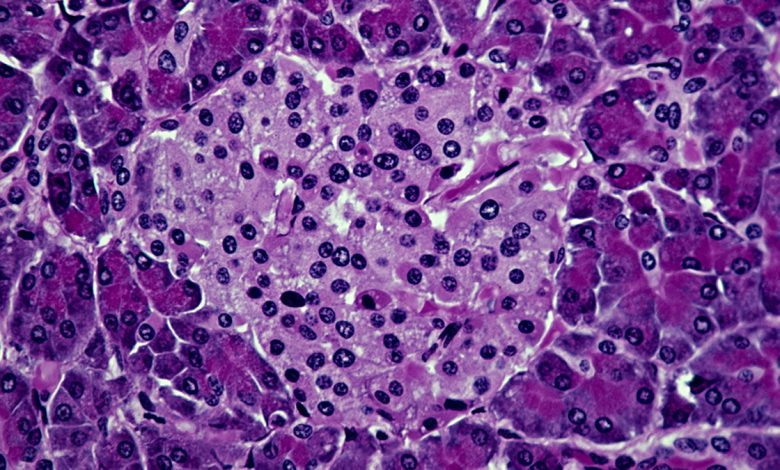

Исследователи из Медицинской школы Стэнфорда, стоящие за этой работой, полагают, что такой же подход может оказаться успешным и для людей. Болезнь возникает из-за сбоя в работе собственной иммунной системы организма, которая атакует производящие инсулин бета-клетки островков поджелудочной железы. В ходе эксперимента иммунную систему мышей перед трансплантацией подготовили с помощью ингибитора иммунитета, низкой дозы радиации и специально подобранных антител. Затем животным пересадили комбинацию кроветворных стволовых клеток и островковых клеток от другого животного.

В результате пересаженные клетки не были атакованы как чужеродные агенты, а иммунная система снова начала функционировать нормально. Учёные подчёркивают, что необходимо не только заместить утраченные островковые клетки, но и перезагрузить иммунную систему реципиента, чтобы остановить их дальнейшее уничтожение. Создание гибридной иммунной системы позволяет достичь обеих целей. Кроме того, ни у одной из мышей не развилась реакция "трансплантат против хозяина" — частое осложнение при пересадке клеток между людьми.